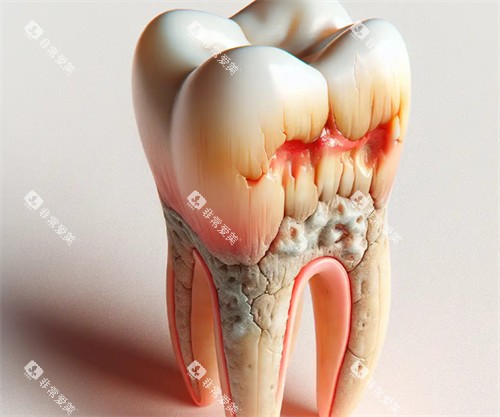

品植口腔专注于牙齿种植和修复,采用小创口技术,减少手术创伤,提高种植成功概率。医院配备特色种植设备,医生团队在种植领域经验充足,适合需要牙齿修复或种植的患者。品植口腔的服务细致,重视术后跟踪,确保治疗改善稳定。